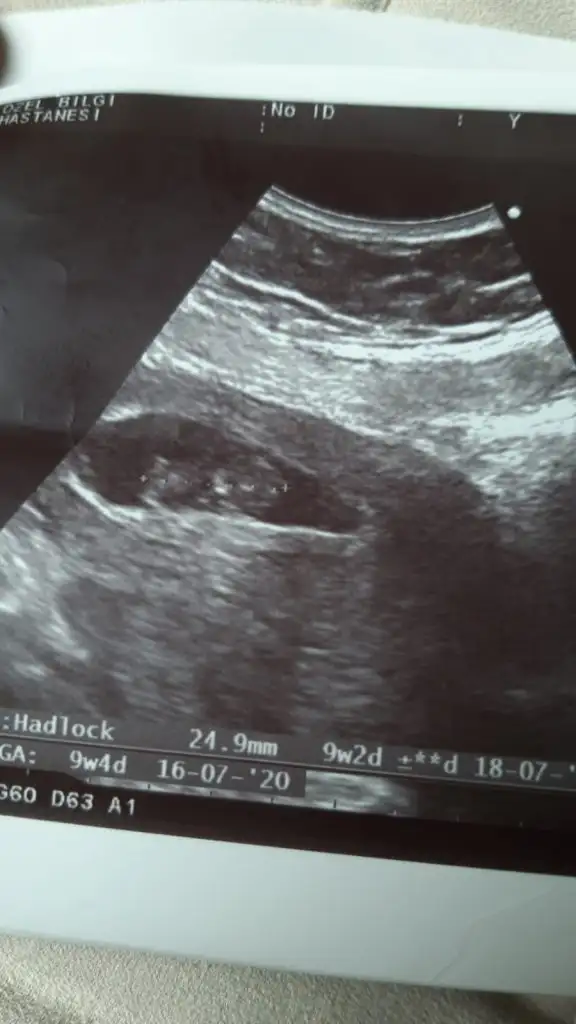

Biri 9+5 biri de 11+5. Yan donmus gibi belli oluyor mu bilemedimTekrar atsana foto

Kız gibiBiri 9+5 biri de 11+5. Yan donmus gibi belli oluyor mu bilemedim![]()

Şekil almamış kız olabilirkizlar buna da yorum yapar misiniz. 10

hafta icinde